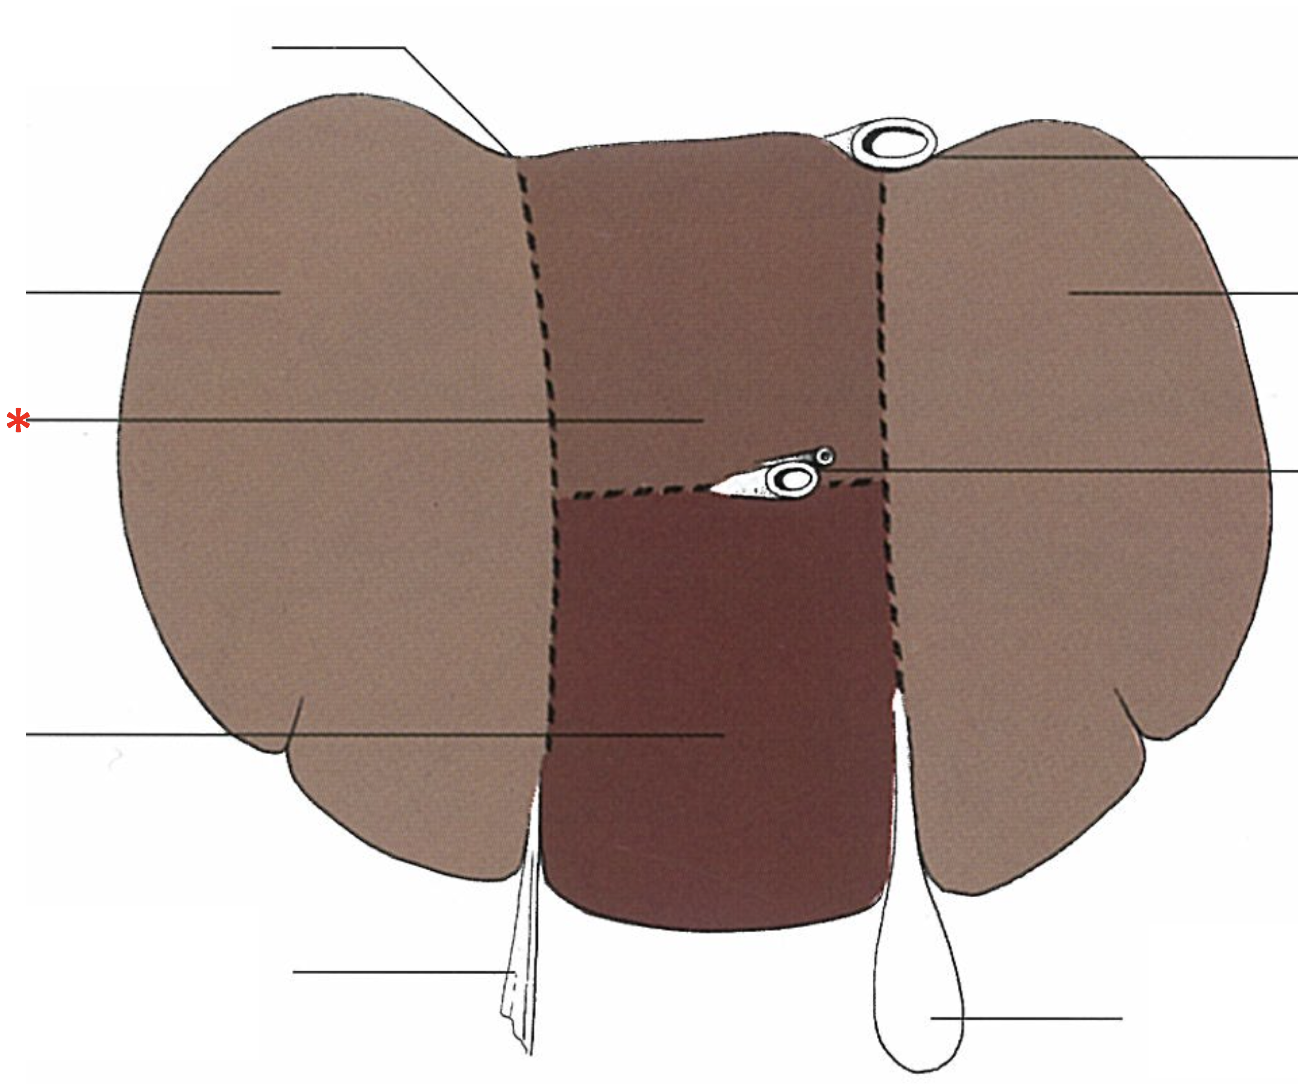

What is shown? Give the Aspect.

Liver of a Cat

Facies diaphragmatica

What is shown? Give the Aspect

Liver of a Cat

Fascies visceralis